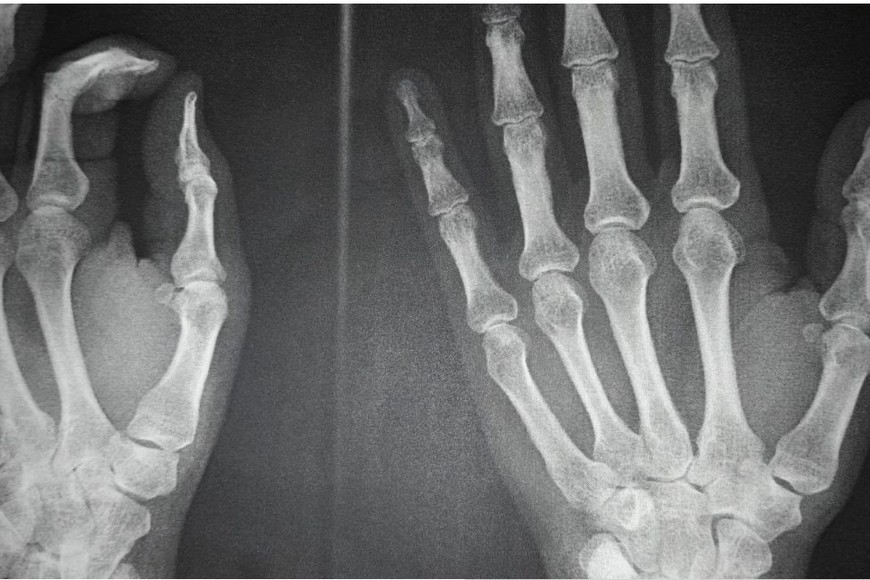

Eduardo, otro de los oficiales heridos, también relató su experiencia. "Estaba sosteniendo una barricada improvisada cuando un golpe muy fuerte me lastimó la mano", explicó. En principio, le diagnosticaron una torcedura, pero al día siguiente una radiografía confirmó que tenía una fractura en el dedo pulgar. "Esto me va a perjudicar en varios sentidos porque tengo que estar varios días fuera de servicio", lamentó.

Diego mencionó que, aunque había rumores sobre posibles incidentes, no esperaban que la situación escalara de esa manera. "Nunca nos pasó algo así. Fuimos siete policías heridos. Uno de mis compañeros terminó con la mano quebrada", comentó. Además, agradeció el apoyo del ministro de Seguridad, Pablo Cococcioni, quien se puso a disposición de los afectados y gestionó su traslado a una clínica privada.